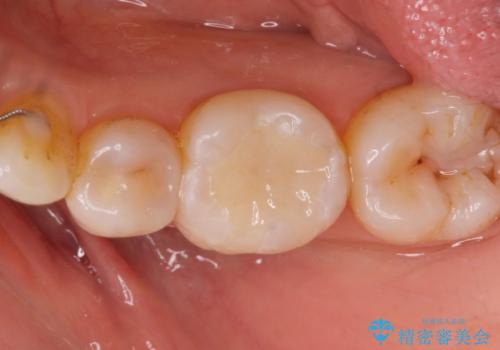

白い詰め物が入り患者様に満足してもらいました。